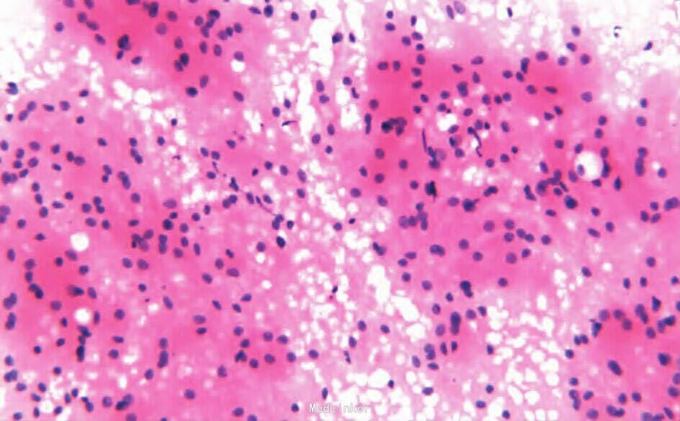

门诊行针吸活检。病理检查镜检:细胞圆形或多角形,细胞之间相互融合成片;胞质丰富,含有明显的嗜酸性颗粒;细胞核较小,圆形或椭圆形,相对居中,大小一致;可见小核仁。细针穿刺标本行免疫组化染色,结果显示S-100核(+),vimentin(+)。细胞学诊断:外阴颗粒细胞瘤,建议手术切除后送病理检查。免疫表型:CD56、CD68、NSE、S-100、vimentin(+),lys(-/+),CD34、NF、desmin均(-),Ki-67增殖指数<5%。病理诊断:外阴颗粒细胞瘤。